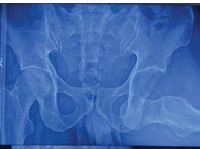

A 45-year-old gentleman sustained a Gustilo-Anderson 3B open right calcaneal intra-articular fracture after a fall from height of approximately 3 m. There were no other bony injuries besides the calcaneal fracture. The calcaneal fracture was initially stabilized with a joint spanning external fixator while the patient underwent multiple surgeries for wound debridement. K-wires were used to reconstruct the subtalar joint, and a cement spacer was utilized to fill the significant bone void (Fig. 1 and 2). Twenty days after the initial injury, the large skin defect was covered using a contralateral anterolateral thigh flap. The external fixator was converted to an Ilizarov circular frame 1 month after soft-tissue reconstruction surgery. Approximately 10 weeks after the initial injury, a biodegradable PCL-TCP synthetic bone scaffold (Osteopore®) was utilized to fill the critical-sized bone defect encapsulated by a pseudomembrane formed by the cement spacer from earlier surgeries (Fig. 3). The scaffold was a custom 3D-printed cuboid-shaped block measuring approximately 8 × 4 × 4 cm which was further cut to fit the exact bony defect. The approximate size of the scaffold needed was based on estimates of the size of the bone defect from pre-operative computed tomography (CT) scans. Autogenous bone graft and bone marrow aspirate concentrate (BMAC) was harvested from the ipsilateral iliac crest and packed into the porous scaffold (Fig. 4). A 6.5 mm cancellous screw was inserted, from the posterior calcaneal tuberosity through the subtalar joint into the talus, to anchor the scaffold (Fig. 5). The Ilizarov circular frame was removed 3 months later. Subsequently, the patient underwent elective removal of the right calcaneal screw and liposuction-assisted debulking of right foot flap 1 year postoperatively.